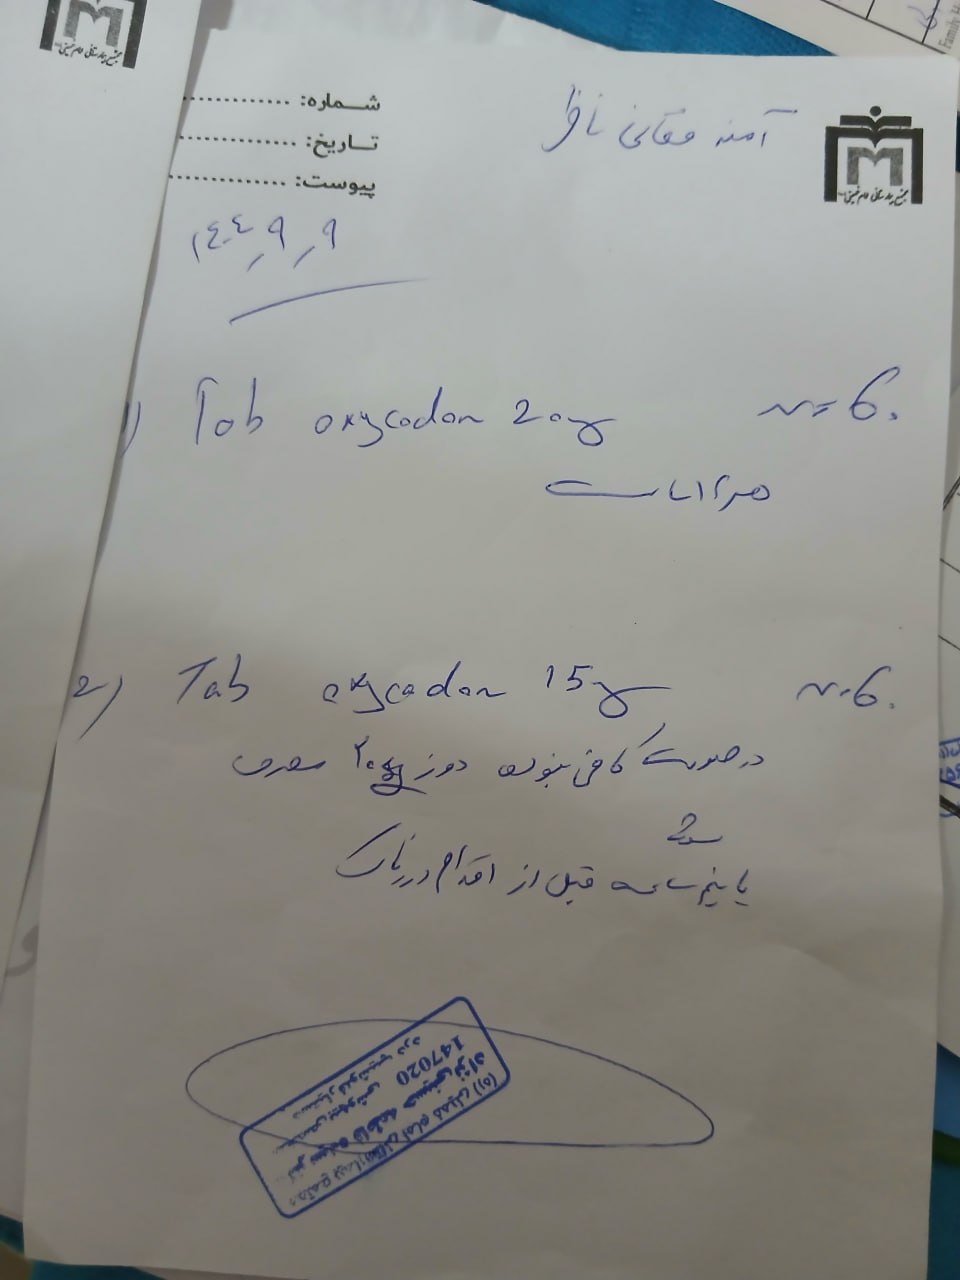

(تصویر مربوط به این مراجعه نیست) Other:

(تصویر مربوط به این مراجعه نیست) Other:

(تصویر مربوط به این مراجعه نیست) Other:

(تصویر مربوط به این مراجعه نیست) Other:

(تصویر مربوط به این مراجعه نیست) Other:

(تصویر مربوط به این مراجعه نیست) Other:

(تصویر مربوط به این مراجعه نیست) Other:

(تصویر مربوط به این مراجعه نیست) Other:

(تصویر مربوط به این مراجعه نیست) Other:

(تصویر مربوط به این مراجعه نیست) Other:

(تصویر مربوط به این مراجعه نیست) Other:

(تصویر مربوط به این مراجعه نیست) Other:

(تصویر مربوط به این مراجعه نیست) Other:

(تصویر مربوط به این مراجعه نیست) Other:

(تصویر مربوط به این مراجعه نیست) Other:

(تصویر مربوط به این مراجعه نیست) Other:

(تصویر مربوط به این مراجعه نیست) Other:

(تصویر مربوط به این مراجعه نیست) Other:

(تصویر مربوط به این مراجعه نیست) Other:

(تصویر مربوط به این مراجعه نیست) Other:

(تصویر مربوط به این مراجعه نیست) Other:

(تصویر مربوط به این مراجعه نیست) Other:

(تصویر مربوط به این مراجعه نیست) Other:

(تصویر مربوط به این مراجعه نیست) Other:

(تصویر مربوط به این مراجعه نیست) Other:

(تصویر مربوط به این مراجعه نیست) Other:

(تصویر مربوط به این مراجعه نیست) Other:

(تصویر مربوط به این مراجعه نیست) Other:

(تصویر مربوط به این مراجعه نیست) Other:

(تصویر مربوط به این مراجعه نیست) Other:

(تصویر مربوط به این مراجعه نیست) Other:

(تصویر مربوط به این مراجعه نیست) Other:

(تصویر مربوط به این مراجعه نیست) Other:

(تصویر مربوط به این مراجعه نیست) Other:

(تصویر مربوط به این مراجعه نیست) Other:

(تصویر مربوط به این مراجعه نیست) Other:

(تصویر مربوط به این مراجعه نیست) Other:

(تصویر مربوط به این مراجعه نیست) Other:

(تصویر مربوط به این مراجعه نیست) Other:

(تصویر مربوط به این مراجعه نیست) Other:

(تصویر مربوط به این مراجعه نیست) Other:

(تصویر مربوط به این مراجعه نیست) Other:

(تصویر مربوط به این مراجعه نیست) Other:

(تصویر مربوط به این مراجعه نیست) Other:

(تصویر مربوط به این مراجعه نیست) Other:

(تصویر مربوط به این مراجعه نیست) Other:

(تصویر مربوط به این مراجعه نیست) Other: